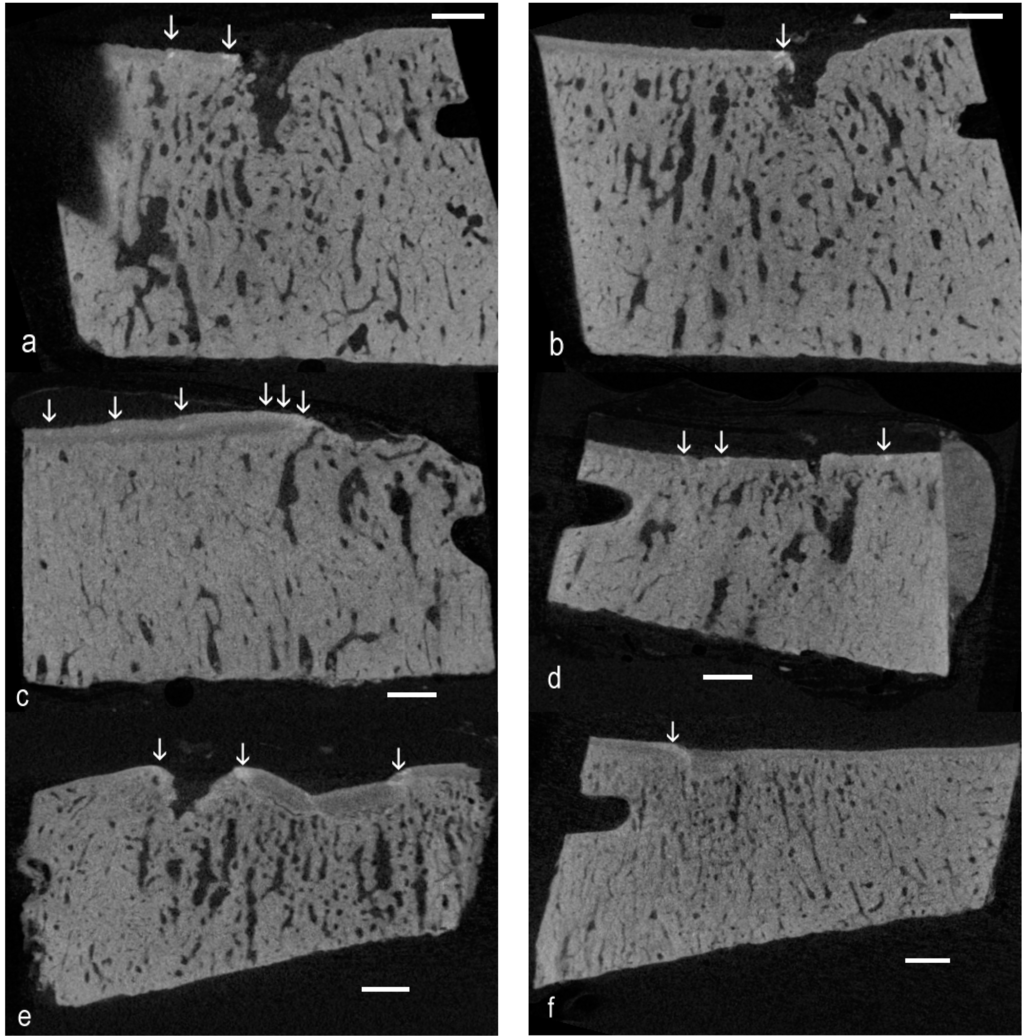

Figure 1 shows unprocessed single XY plane images from Z stacks in which there are localized patches with higher density below the level of the mineralizing front (MF) of the ACC. Examples are also shown where there is a local elevation of the MF with no noticeable change in the grey level, so that although it is a protrusion, it is not obviously hyperdense.

Figure 1. Unprocessed single XY plane images from Z stacks in which there are localized patches (vertical arrows) with higher density below the level of the mineralizing front of the articular calcified cartilage (ACC). Scale bars = 1 mm. (a) Eight-year-old, which showed the highest number of easily-spotted high-density mineral infill (HDMI) fields in a control sample; (b) Parallel slice at 360 µm; (c) Advanced OA, five-year-old; (d) Advanced OA, four-year-old; (e) Early OA, two-year-old; and (f) Early OA, same two-year-old, but in the more palmar core.

2.4. Improving Confidence in Identifying Hyperdense Regions in Noisy µCT Image Stacks

We define “hyperdense” on the basis that image grey levels are “whiter” (the mineral content is higher) than is found in surrounding ACC, in which values are usually above those in SCB. Whereas protrusions (oblique arrows in Figure 2) may be spotted on the basis of morphology, high-density inclusions (vertical arrows in Figure 1 and Figure 2) in ACC are more difficult to see in single image planes. However, XY plane images adjacent in Z can be averaged to provide mean values, greatly increasing confidence in spotting above normal values.